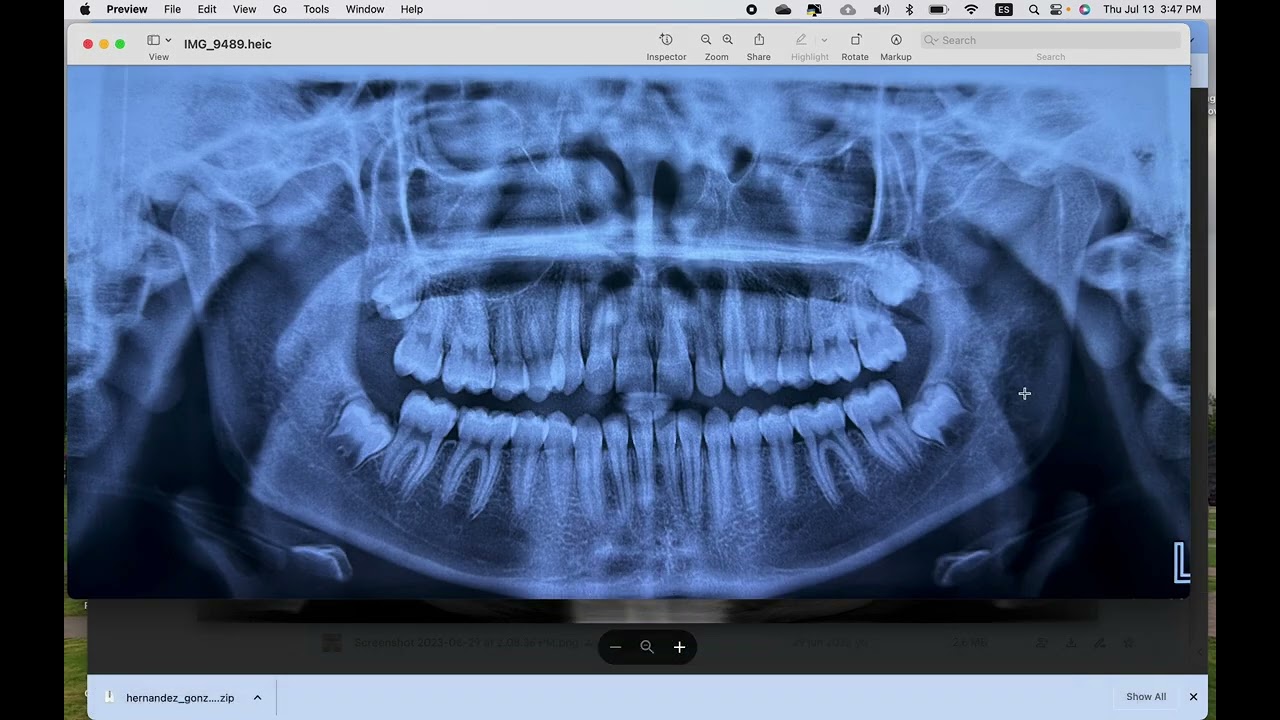

Si tiene alguna pregunta no dude en escribirme. Recuerde que para emitir un diagnóstico, tratamiento o presupuesto es necesario realizar una evaluación clínica y radiográfica previamente. Atendemos pacientes con seguro DENTEGRA, CENTAURO.